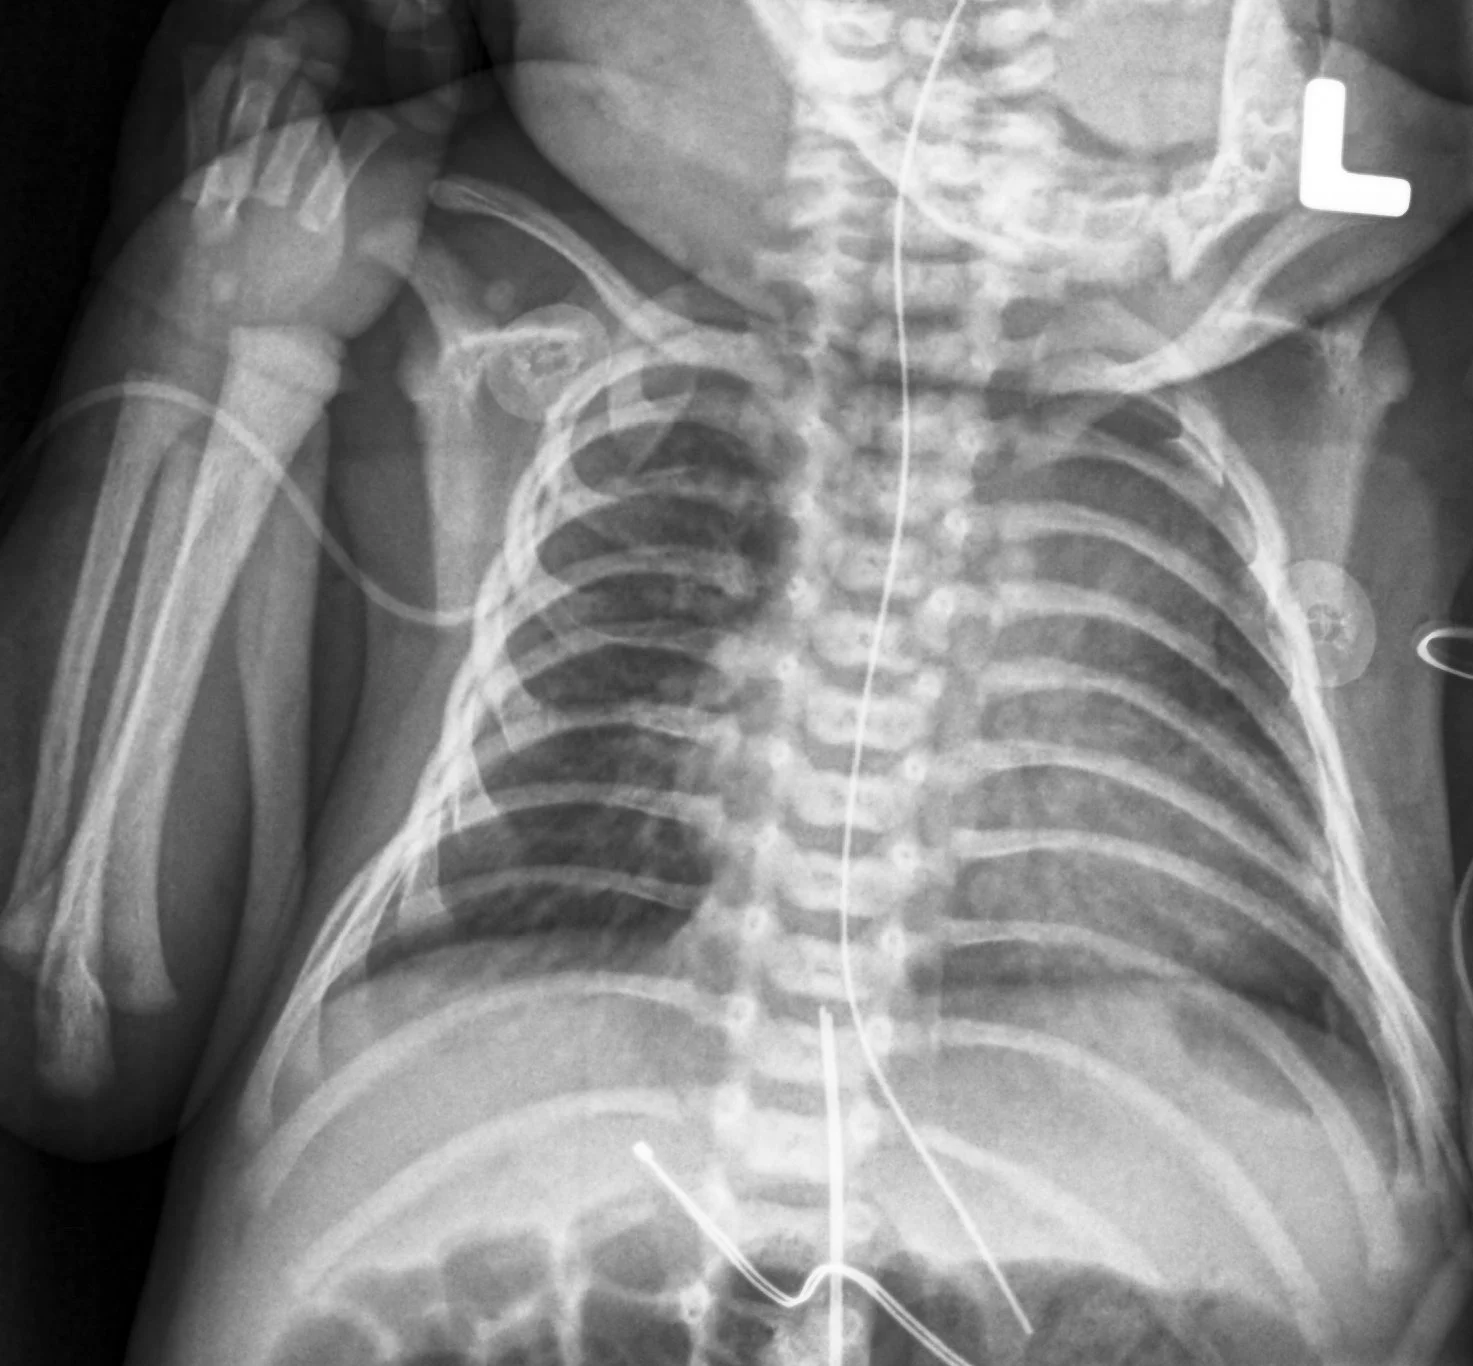

When it comes to children’s health, accurate diagnosis is extremely important. Therefore, pediatric X-ray and imaging play a vital role in detecting, monitoring, and managing various medical conditions in infants, toddlers, children, and adolescents. At Sparsh Hospital, under the expert guidance of Dr. Sneha Vaswani, we provide safe, precise, and child-friendly pediatric X-ray and imaging services designed specifically for young patients. Moreover, our advanced imaging facilities ensure quick diagnosis while prioritizing the comfort and safety of every child.

Pediatric imaging refers to medical imaging techniques specially adapted for children. Since children’s bodies are still developing, imaging requires specialized protocols, equipment, and expertise. Therefore, Sparsh Hospital follows internationally accepted pediatric imaging standards to minimize radiation exposure while maximizing diagnostic accuracy.

X-ray imaging is often the first step in diagnosing many pediatric conditions. Therefore, Sparsh Hospital offers low-dose digital pediatric X-ray services that are both safe and highly accurate.

Moreover, our digital X-ray technology provides high-resolution images with minimal radiation exposure.